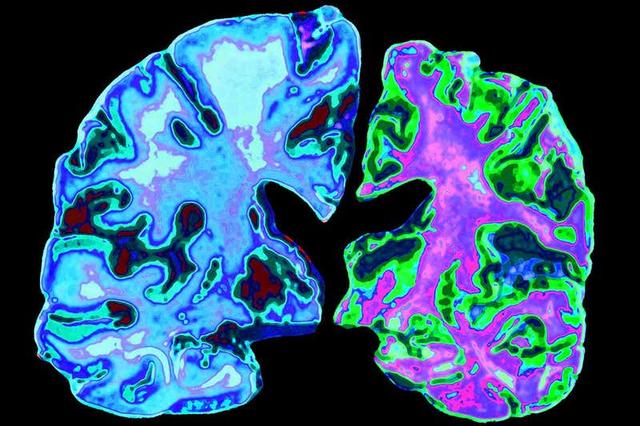

Alzheimer’s disease causes damaged to the brain (right)

JESSICA WILSON/SCIENCE PHOTO LIBRARY